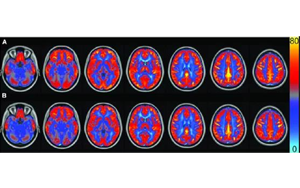

顱腦創(chuàng)傷后的繼發(fā)性腦損傷是怎么發(fā)生的?Science:補(bǔ)體介導(dǎo)炎癥及神經(jīng)損傷!

創(chuàng)傷性腦損傷 (TBI)是導(dǎo)致兒童和成人殘疾的主要原因之一。每年,TBI 影響著全球6900余萬(wàn)人,可能導(dǎo)致認(rèn)知功能障礙、感覺(jué)處理困難、睡眠中斷和癲癇等不良后果。其中大多數(shù)在TBI發(fā)生后數(shù)月或數(shù)年由繼發(fā)性損傷引起。TBI的原發(fā)損傷本質(zhì)上是不可逆轉(zhuǎn)的,因此,了解繼發(fā)性損傷發(fā)生的時(shí)間、節(jié)點(diǎn)和機(jī)制對(duì)于預(yù)防或治療TBI后殘疾至關(guān)重要。